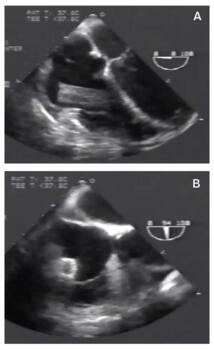

A 58-year-old male with recently diagnosed superior vena cava syndrome secondary to lymphoma underwent stenting with a 60 x 16 mm self-expanding Wallstent (Boston Scientific) in the superior vena cava for worsening of facial plethora and swelling of upper extremities. Two days post procedure, the patient returned to our facility with severe dyspnea and return of the original symptoms after reaching for an object on a nearby table. On physical examination, a new systolic murmur was noted in the fourth left intercostal space. The heart rate was 110 beats/min, with a blood pressure at 145/86 mm Hg. Frequent premature ventricular contractions were noted on electrocardiographic monitoring. Possible stent migration was suspected, which was confirmed on transesophageal echocardiography (Figures 1A and 1B; Videos 1 and 2). The patient underwent successful stent removal with snaring, as well as subsequent placement of another stent in the superior vena cava without further complications.